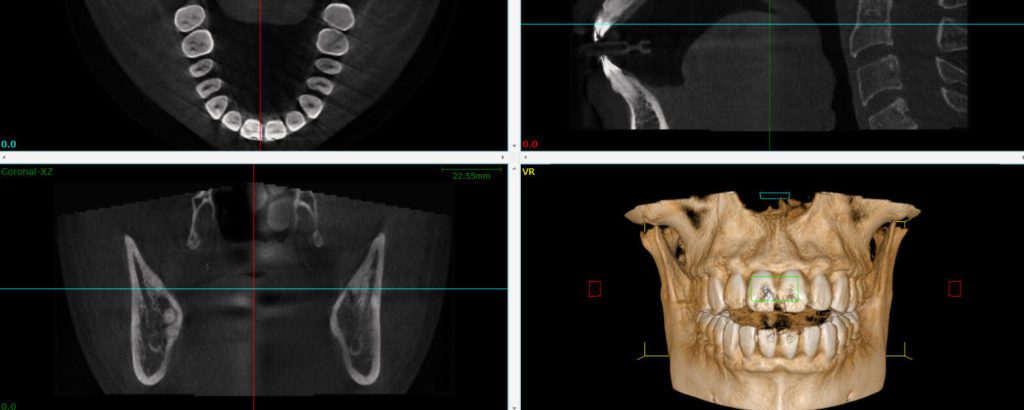

Seeing Inside the Bone with a 3D Cone CT Scan

A cone beam CT creates a 3D view and cross sections of the target area. The information it provides is critical for a number of situations, including placing dental implants, performing a complex root canal or extraction, or searching for the source of pain or infection. CBCT gives us the information we need about your condition before a dental procedure.